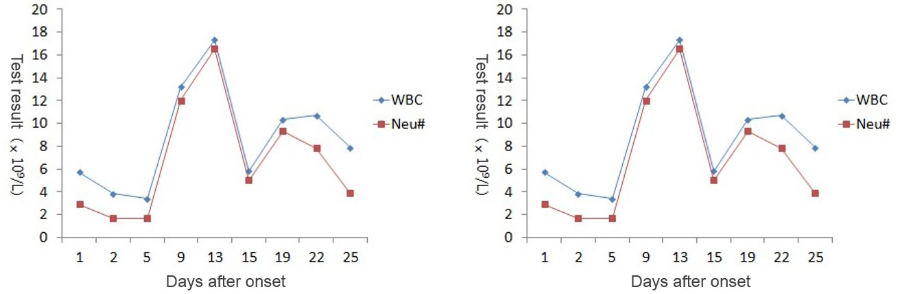

During the whole process of diagnosis and treatment, the patientŌĆÖs clinical manifestations and chest CT scan results have been recorded (see Table 1), and so are CBC and CRP results (see Figure 1).

The patient had a low fever at the time of the initial examination, but the WBC count and lymphocyte count were normal, suggesting that the patient was in the early stage of COVID-19 at that time.

As the patientŌĆÖs health deteriorated, the white blood cell count (WBC#) and neutrophil count (Neu#) increased sharply after a slight decline, while the lymphocyte count (Lym#) continued to decline. The Neutrophil-to-Lymphocyte Ratio (NLR) rose rapidly while the CRP value goes up. At the most critical moment (the 13th day after the onset of symptoms), WBC#, Neu#, NLR and CRP reached their peaks respectively, with Lym# at the lowest point.

After proper medical treatment and caring, the patient gradually recovered, with rapid decline of WBC#, Neu#, NLR and CRP. In contrast, Lym# gradually increased. On the 25th day, WBC#, Neu#, NLR, Lym# and CRP all returned to normal range. Although CT scan showed that the lesions in lungs hadnŌĆÖt completely disappeared yet, the patient was already able to move without oxygen therapy. Most importantly, the nucleic acid test result turned negative.

An NLR greater than 3.13 can be used as an independent predictor for the exacerbation of patients with COVID-19. The finding of this case is consistent with that in the study published by Ditan Hospital. The patientŌĆÖs NLR was higher than 3.13 from the 9th day to the 22nd day, and the NLR drops below 3.13 on the 25th day. In this case, PCT was monitored on Day 5, 13, and 22, all of which were lower than 0.5 ng/mL, indicating that no serious bacterial infection occurred.

The CBC and CRP change exactly in line with the law of disease development during the diagnosis and treatment of COVID-19 patients. Monitoring these routine laboratory test results, including WBC, Lym#, NLR and CRP, during the hospitalization period is helpful for managing patientŌĆÖs medical treatment and prognosis.